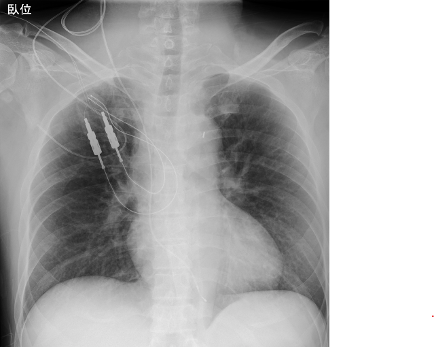

【胸部レントゲン】

心胸郭比65%、肺門部血管陰影の増強、左右肋横隔膜角/鈍